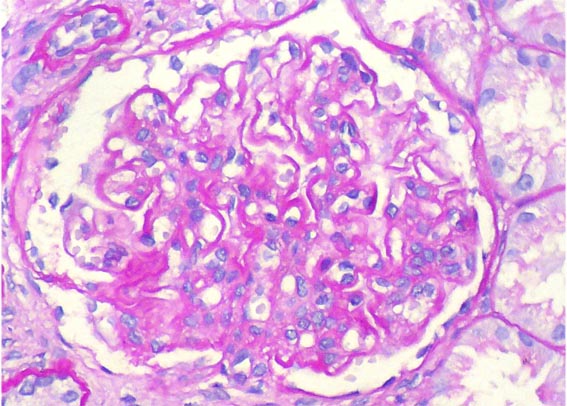

Figura 4.

Tricrómico de Masson, X400.

Figura 5.

El mismo glomérulo de la imagen anterior, amplificada. Tricrómico

de Masson, X400.